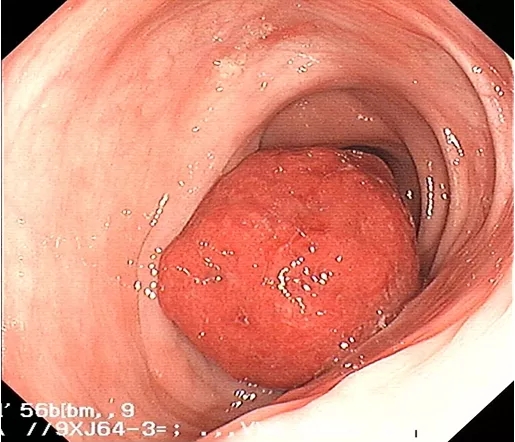

经小瑞家属签字同意后,经过周密的检查前准备,消化内科黄理副主任医师及陈丽芬副主任医师带领内镜中心医护团队,联合麻醉科,共同为患儿实施全麻下无痛胃肠镜检查。术中,镜下可见横结肠距肛门55cm处见一大小约4.0cmX4.0cm的息肉,几乎堵住整个肠腔。原来小瑞的这些症状竟是结肠巨大息肉在“作祟”,在征得家长的同意后,黄理副主任医师及陈丽芬副主任医师凭着丰富的经验、娴熟的手术操作,将整块息肉完整切除。同时,麻醉师也在为小儿实施精准麻醉,确保术中患儿稳定,全程30分钟,手术非常顺利。术后五天患儿痊愈出院,病理结果提示:(横结肠)幼年性息肉。

肠镜下可见图像